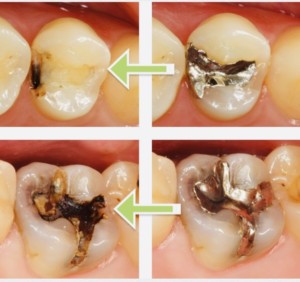

歯と歯の間のむし歯はなかなか判断が難しく、視診のみではX線を併用さした場合の50%以下しか隣接面のむし歯を検出できません。

佐賀市の歯医者、当院こども歯科医院ではX線の咬翼法により隣接面むし歯を検出しています。

これにより象牙質に至るむし歯の90%以上が検出されます。